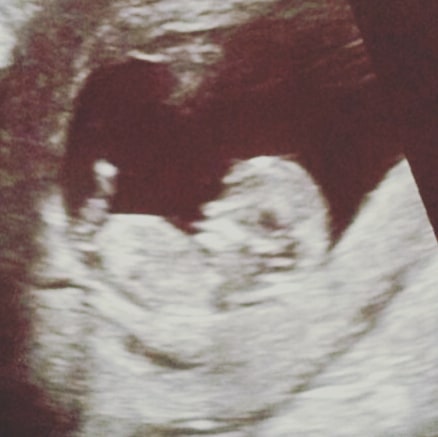

Es traf uns (trotz aller Vernunft) unerwartet. Nach der 8.SW hatten wir das Herzchen schlagen sehen. Dieses kleine Wesen in meinem Bauch gehörte schon zu uns, wir feierten gemeinsam Weihnachten und Silvester – so gut man das als Schwangere trotz Übelkeit und diverser Abstinenzen eben kann.

Gott sei Dank nahm sich dieser Arzt sehr viel Zeit für mich. Er schaute lange per Ultraschall und stellte wenige Fragen.

Da war kein Herzschlag mehr.

Das kleine Wesen war schon seit circa zwei Wochen nicht mehr gewachsen.